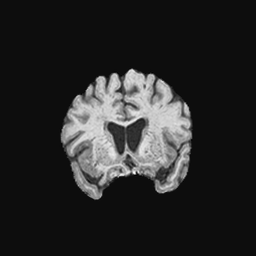

Exp. 1: Segmented adult brain data is used to evaluate our network’s regression performance with known ground truth . 85 brains from the ADNI data set[1] were randomly selected; 70 brains for and 15 brains for . Fig. 2 shows an example slice of the ground truth and the reconstructed .

Reconstructing from initialisation without SVR yields a PSNR of 23.7 1.09; with subsequent SVR the PSNR increases to 29.52.43 when tested on 15 randomly selected test volumes after four iterations of SVR.

0..5.1 Exp. 1:

Slices, extracted from a correctly registered and reconstructed 3D volume, from the testing data set are presented to the network. The predicted slice is extracted from the same volume, using parameters estimated by SVRNet as shown in Fig. 8 and 9.